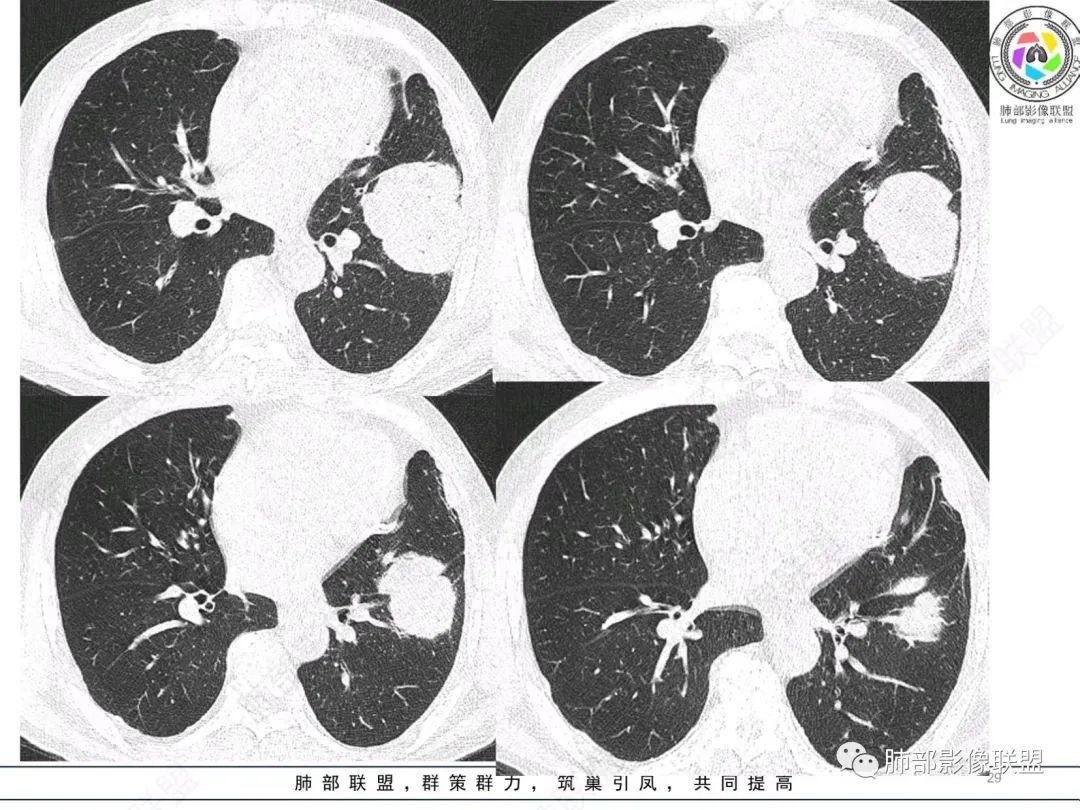

左肺上叶胸膜下肿块,宽基底与胸膜相连,跨叶裂,边缘清晰膨隆,其内支气管充气,部分扩张、僵直,无明显强化,血管造影征,考虑淋巴瘤,鉴别腺癌

左肺胸膜下巨大占位,跨叶裂,宽基底与胸膜相连,胸膜钙化,平扫密度较低,强化不明显,可见内部血管显影,支气管充气征和扩张,考虑为恶性,倾向于淋巴瘤

左肺上叶肿块,宽基底与胸膜相连,跨叶裂,边缘清晰膨隆,可见小分叶,其内支气管充气,部分扩张、僵直,呈枯枝征,支气管达边征,增强无明显强化,可见血管造影征,考虑恶性病变,淋巴瘤,鉴别粘液腺癌。

我要修正一下观点了:仔细看了视频,肿块占位效应明显,对周围血管,支气管有推挤,增强后强化不明显,NSE增高,半年体重下降25公斤,虽然有内部支气管扩张,血管漂浮,边界清楚支持淋巴瘤,但强化太低,膨隆,占位推挤太明显(淋巴瘤一般没有这么明显的占位效应),胸膜关系有载桩,恶病质明显(乏力,半年体重下降了25公斤),NSE也明显增高,就不支持淋巴瘤了。还是考虑外朝内的恶性肿瘤,间质来源的肉瘤伴有神经内分泌分化或者大神泌。

不支持淋巴瘤的有四点:1、对周围血管支气管推挤明显。2、胸膜有栽桩,3、强化太弱(淋巴瘤一般还是中度以上甚至高度强化多见),4、NSE升高明显,体重下降太明显。

我再建一下血管。支气管进入,但是近端推移,堵塞

肺动脉推移为主,边缘部分进入

大肿块、表面光滑但深分叶,肺门侧支气管堵塞

回头看,内部支气管近端其实不连续,伴随肺动脉不存在

这两点就不符合

还有如果从支气管的特点考虑黏膜相关性淋巴瘤,其整体应该是边缘不清楚为主,肺炎样为主。

4)密度:肿块平扫为软组织密度,由于体积较大,内部常见大片状坏死,可出现不规则厚壁空洞或坏死内多发无壁小空洞,坏死多不均匀:坏死灶内可见如柳絮样的斑片样强化灶,坏死边缘与非坏死区分界不清本例坏死较明显,密度不均匀。

5)肿瘤强化方式:肺部恶性肿瘤强化程度与其血供丰富程度相关,血供丰富多强化明显,反之则较差。由于PSC 周边实性部分富血供及内部黏液变性、坏死,增强后肿块多数呈轻-中度边缘环形强化或不均匀小斑片状强化。国外学者对照病理发现肿瘤细胞或胶原组织增强扫描时强化,无强化的低密度区代表了黏液样变性区和出血坏死区。